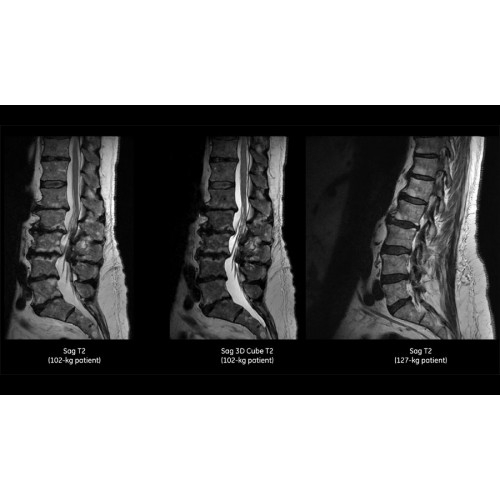

Более низкая стоимость эксплуатации — SIGNA Pioneer потребляет на 50% меньше электроэнергии, чем обычные МРТ 3.0Т, при этом обеспечивается высокая производительность благодаря инновационной технологии сверхэффективной градиентной системы.

Система обеспечивает легкое сканирование, автоматическую оптимизацию протоколов, простой и автоматизированный рабочий процесс сканирования при задержке дыхания.

Снижение количества артефактов и, как следствие, уменьшение повторных сканирований.